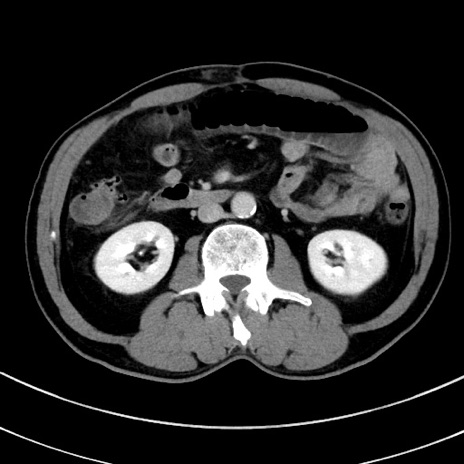

症例8(横断像)

【症例】 60歳代男性

【主訴】 黒色吐物

【現病歴】 4日前から嘔気自覚、2日前の朝食後にも嘔気あり、自分で手で嘔吐反射起こし嘔吐したところ血が混ざっていたため受診。

【既往歴】 5年前汎発性腹膜炎を伴う急性虫垂炎で手術、高血圧、前立腺肥大症、高脂血症

【身体所見】 腹部正中に手術癩痕あり 腹部平坦・軟圧痛なし膨満感あり

【データ】WBC 8400、CRP 4.54